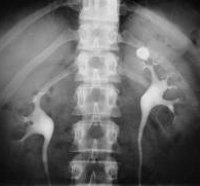

N20.0 Камни почки